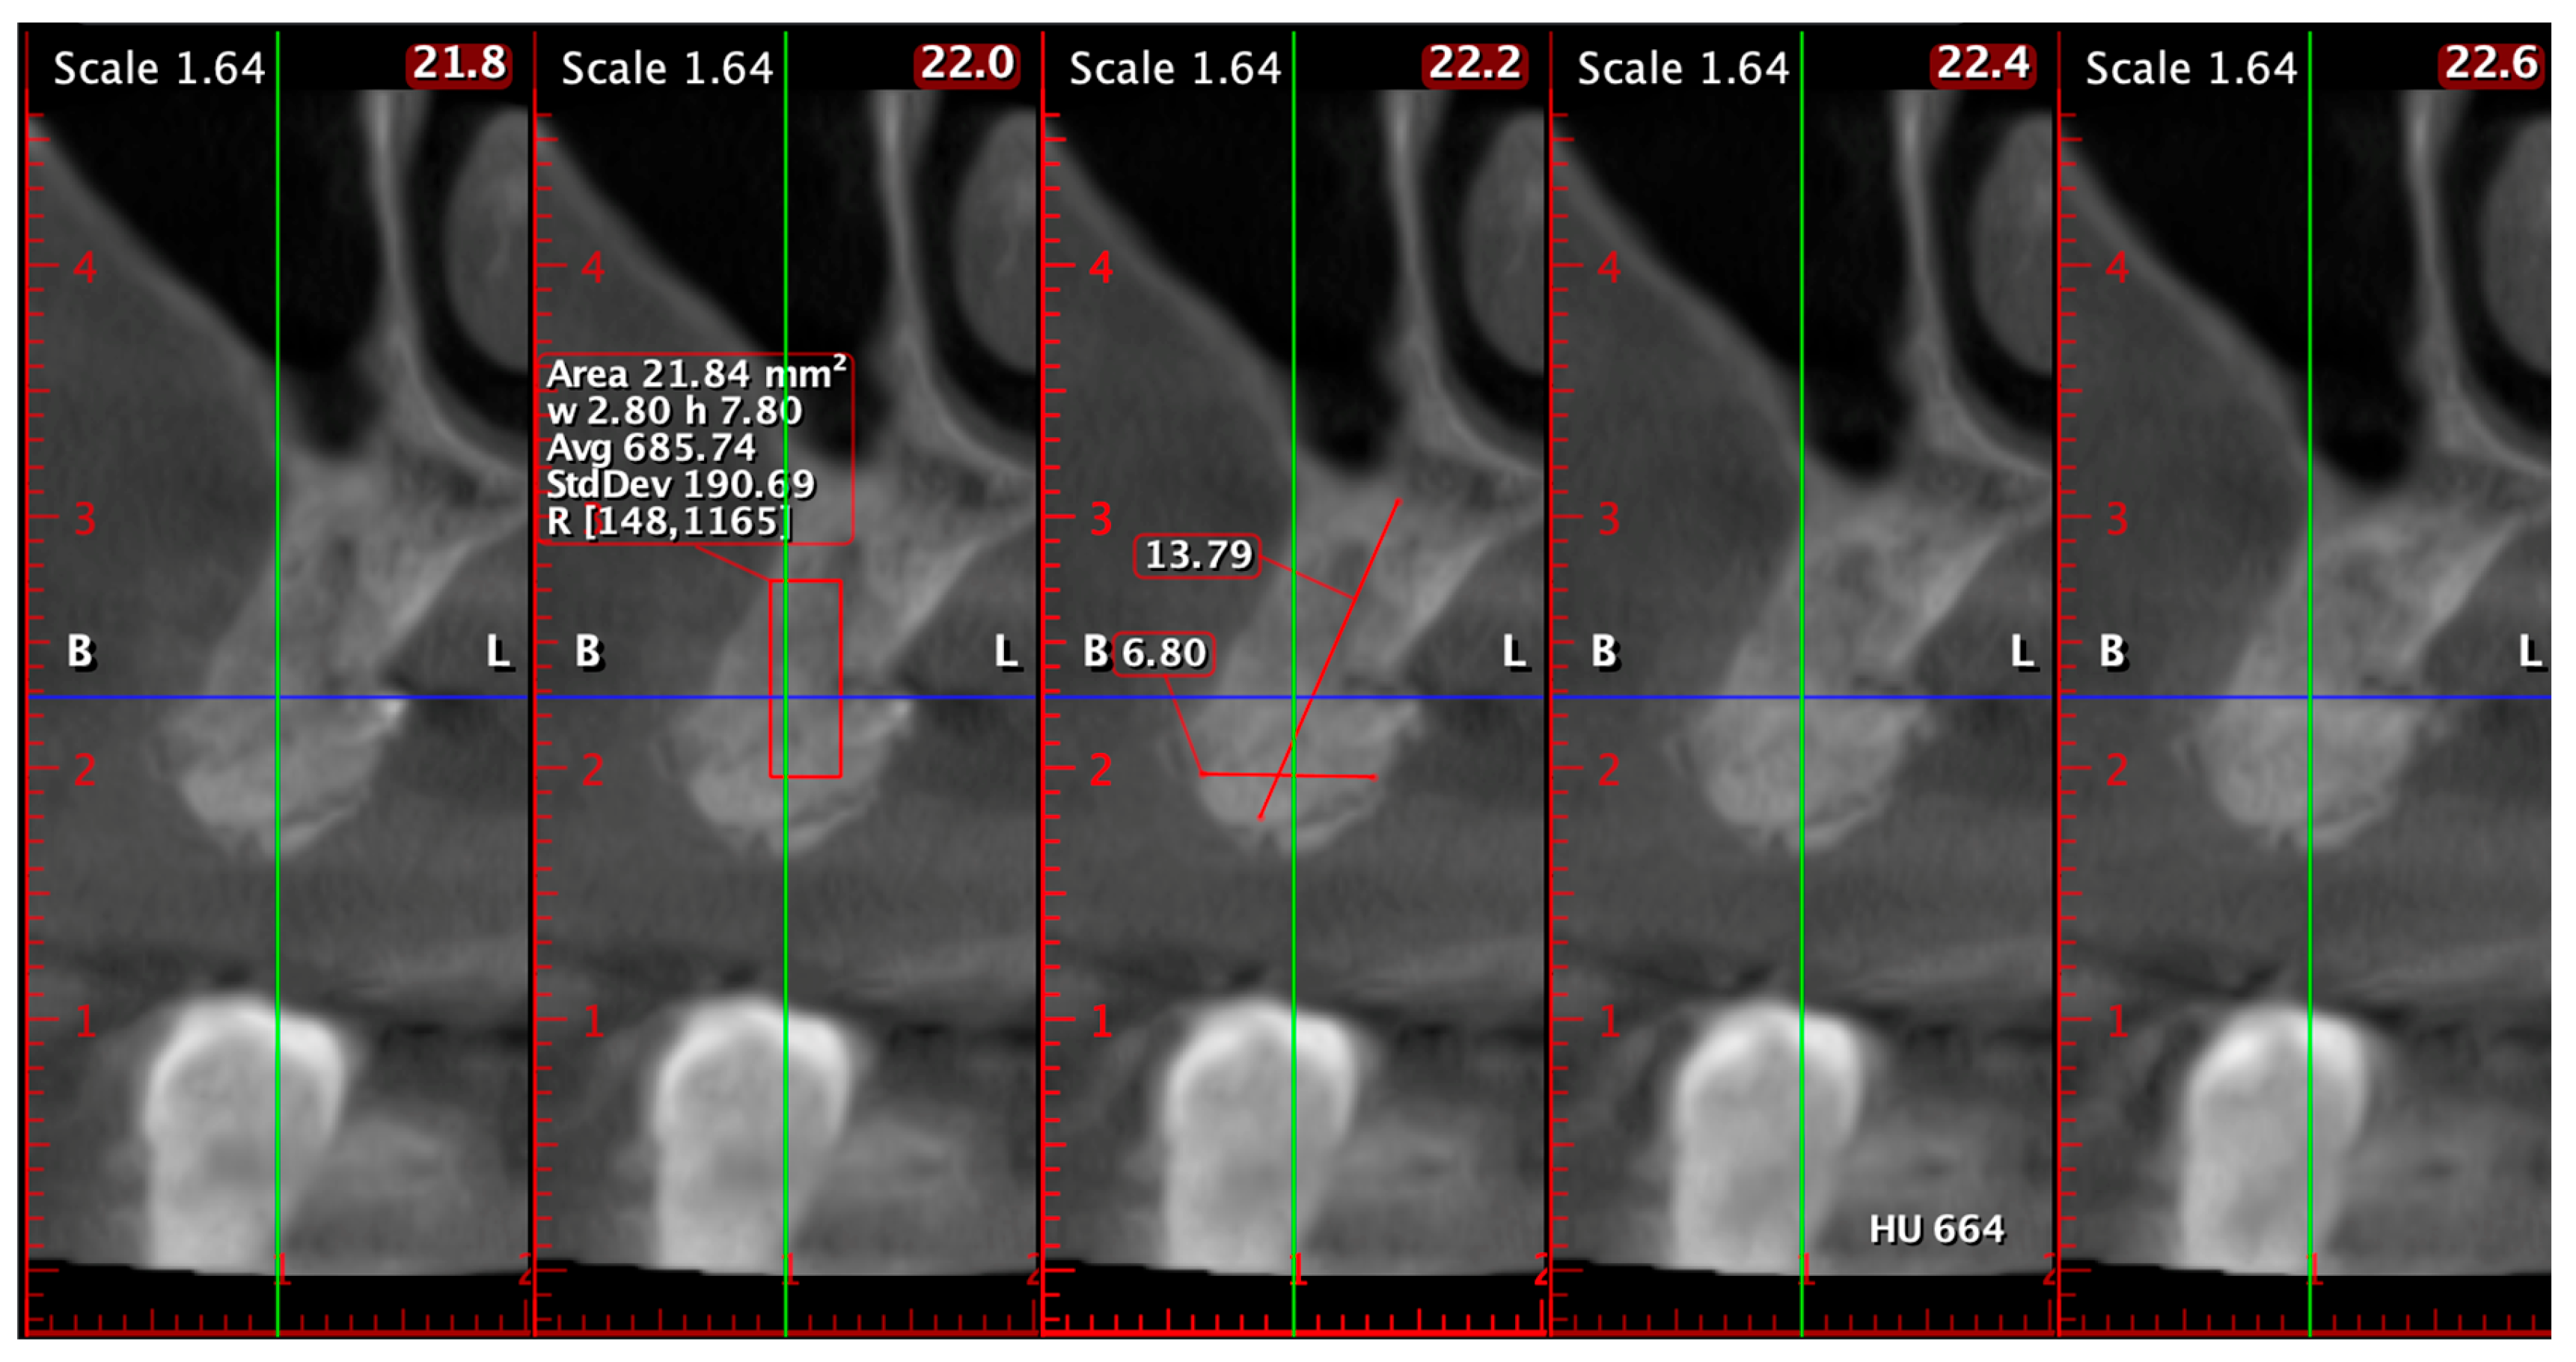

In another case, CBCT assessment of the posterior maxilla confirmed successful vertical and horizontal regeneration (Figure 14). At 6 months postoperatively, the bone height from the alveolar crest to the sinus floor measured 13.79 mm, while the bucco-palatal ridge width reached 6.80 mm. The mean trabecular density was 685.74 HU, with a density range of 148 to 1165 HU, indicating well-mineralized trabecular bone and developing cortical structures. The radiologic findings demonstrated excellent graft integration and volume preservation, sufficient bone height and width to allow safe and predictable implant placement, and favorable bone quality in a region traditionally considered challenging due to low baseline density.

Figure 14. CBCT evaluation of the posterior maxilla at 6 months postoperatively: vertical ridge height (13.79 mm), bucco-palatal width (6.80 mm), and average trabecular density of 685.74 HU, indicative of mature regenerated bone suitable for implant insertion.